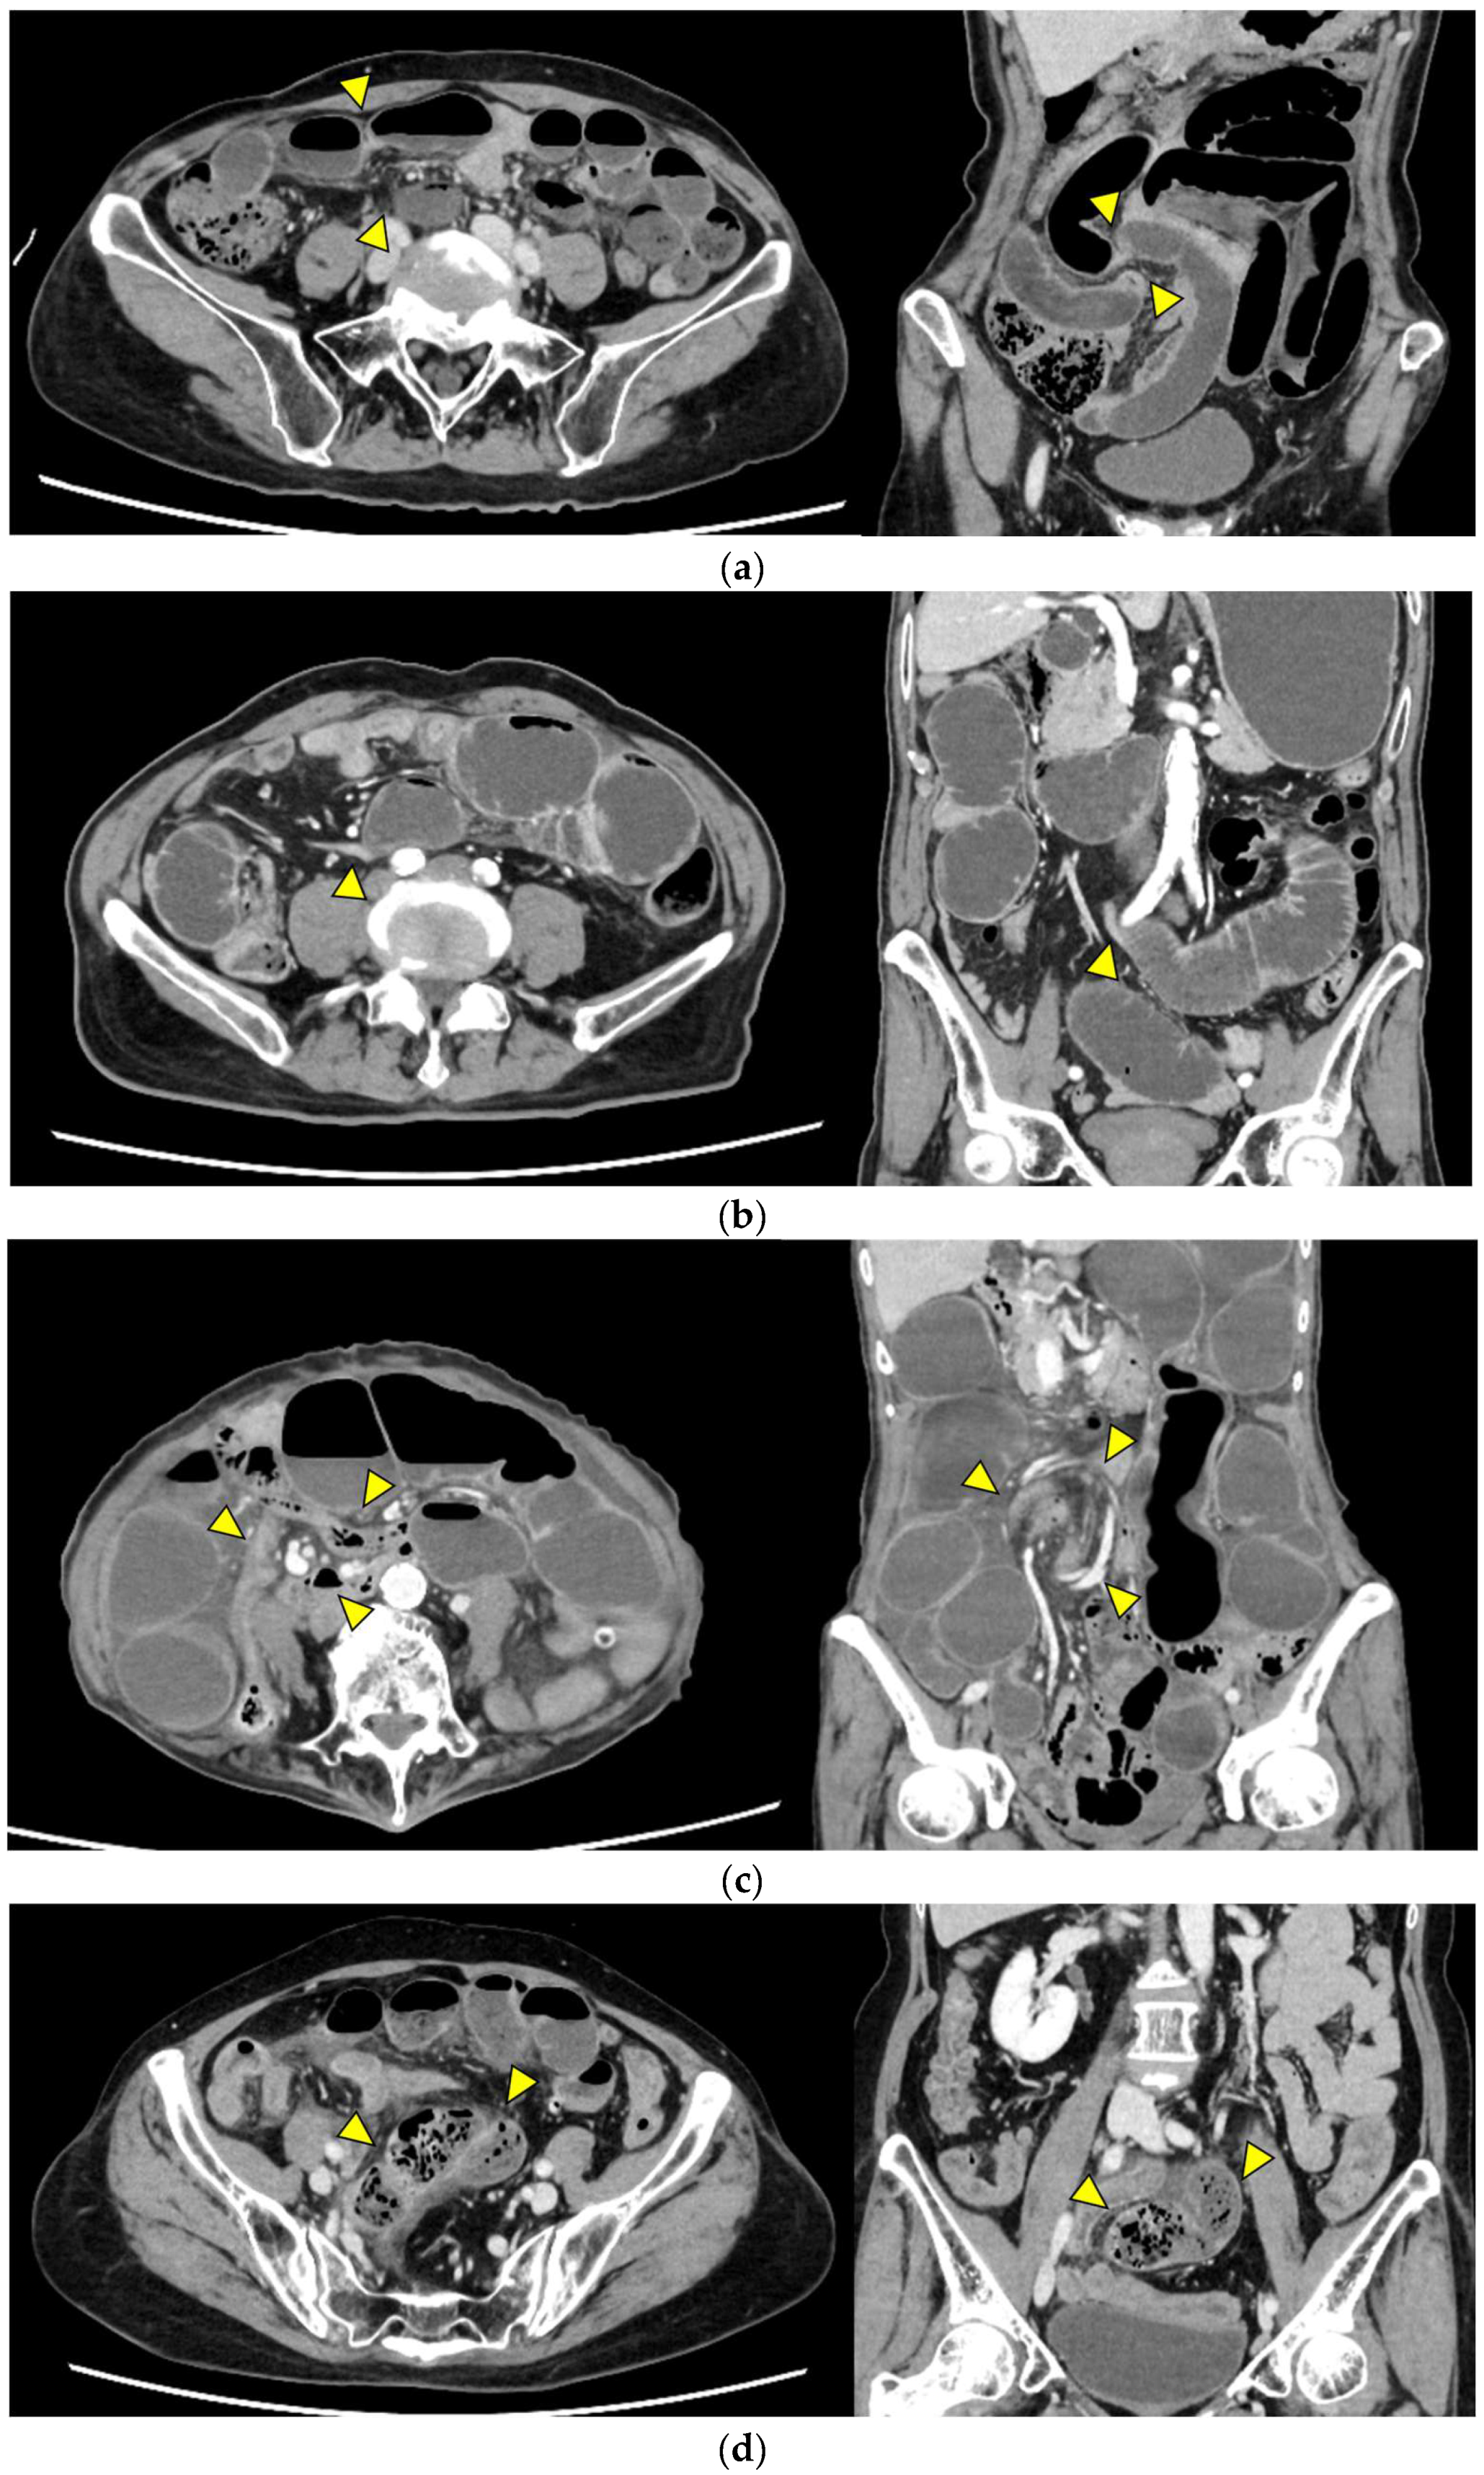

Representative images are presented in Figure 1.

• Closed loop (Figure 1a): A dilated U- or C-shaped bowel segment with two transition points in close proximity, often associated with radial distribution of mesenteric vessels. This configuration may carry a high risk of rapid progression to strangulation and ischemia, requiring prompt surgical consideration.

• Beak sign (Figure 1b): Gradual tapering of the bowel lumen or contrast column at the obstruction point, typically indicating torsion or sharp angulation. This sign localizes the obstruction and often reflects mechanical blockage due to adhesions or volvulus, which may progress to ischemia if left untreated.

• Whirl sign (Figure 1c): Swirling of mesenteric vessels and fat, suggestive of volvulus or twisted mesentery. Presence of this sign strongly suggests torsion with compromised mesenteric blood flow.

• Small bowel feces sign (Figure 1d): Mixture of gas and particulate matter (resembling feces) within a dilated small bowel loop proximal to the obstruction, indicating delayed transit. This sign indicates subacute or prolonged obstruction, but does not necessarily imply ischemia.

• Mesenteric edema (Figure 1e): Increased attenuation and stranding of mesenteric fat surrounding the affected loop, typically reflecting venous congestion. This is an early indicator of impaired venous outflow and increased risk of ischemia, requiring close monitoring and a low threshold for surgical intervention if clinical deterioration occurs.

• Mesenteric vessel engorgement (Figure 1f): Prominent or dilated mesenteric veins near the involved segment, suggestive of impaired venous outflow or strangulation. Venous congestion typically precedes arterial compromise, and the presence of this sign indicates evolving mesenteric ischemia.

• Absent bowel wall enhancement (Figure 1g): Complete absence of bowel wall enhancement on contrast-enhanced CT, which is highly suggestive of transmural infarction. This is a critical sign of irreversible ischemia and generally indicates the need for immediate surgical intervention.

• Blurred Kerckring folds (Figure 1h): Indistinct mucosal folds (valvulae conniventes) in dilated small bowel loops, often associated with ischemic edema. Blurring of mucosal folds reflects mucosal/submucosal injury from ischemia and impending bowel damage due to severe obstruction.

• Ascites (Figure 1i): Free peritoneal fluid, either localized around the affected loop or diffusely distributed, is frequently associated with advanced ischemia. Increasing ascites in the obstruction setting often indicates transmural ischemia or severe inflammation.

Figure 1. Representative CT findings suggestive of SSBO. Yellow arrowheads highlight the relevant findings. (a) Closed loop; (b) beak sign; (c) whirl sign; (d) small bowel feces sign; (e) mesenteric edema; (f) mesenteric vessel engorgement; (g) absent bowel wall enhancement; (h) blurred Kerckring folds; (i) ascites.